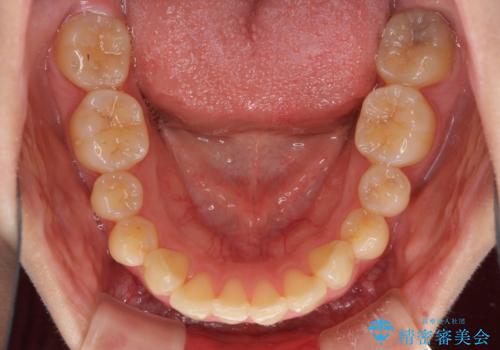

- 口元の突出感改善を希望して来院された患者様です。

口元を積極的に引っ込めるために、上下左右の小臼歯計4本を抜歯することとしました。

咬み合わせが深いため、咬み合わせの高さを向上させながら口元を下げることとしました。

左右ともに下顎に対して上顎歯列が前方位にある上顎前突であったので、上顎歯列全体を後方に移動させることで上下咬み合わせを改善し、その上で抜歯矯正により口元の突出感を改善させていきました。